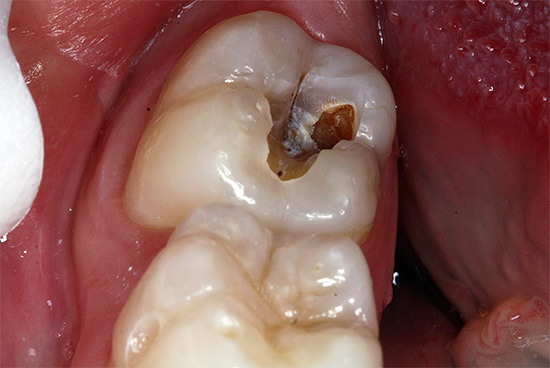

- La carie media cronica è caratterizzata da un'ampia cavità che colpisce la dentina. In questo corso, la cavità non ha ammorbidito la dentina, ma solo pigmentata dentina cariata. Il fondo è denso con lievi sporgenze e rugosità, che indica un processo lento nella fase di compensazione a causa della sostituzione della dentina.

- La carie cronica profonda differisce dalla media solo per la profondità della cavità. Inoltre non ha bordi a smalto sporgenti, generalmente ben lucidati.

Con carie medie e profonde, la dentina necrotica e lo smalto pigmentato vengono rimossi. Se la cavità pulita risultante è relativamente piccola, viene disinfettata e quindi riempita con materiale di riempimento. Con una grande cavità o la distruzione di una o più pareti del dente, vengono posizionate le linguette o, in alcuni casi, le corone.